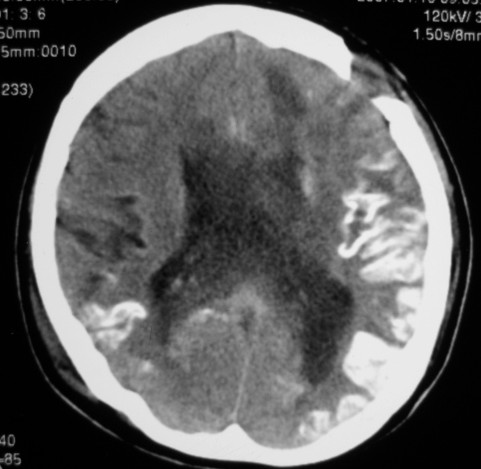

标题: CT9218:男性,50岁,脑出血术后复查,两次片相隔半月,请分 [打印本页]

标题: CT9218:男性,50岁,脑出血术后复查,两次片相隔半月,请分

第一次ct片脑出血术后,出血吸收期。第二次ct 片左颞顶枕部及右颞顶部有脑回样高密度影。考虑珠网膜下腔出血。脑出血术后改变,脑出血恢复期 并脑积水。

第一次ct片脑出血术后,出血吸收期。第二次ct 片左颞顶枕部及右颞顶部有脑回样高密度影。考虑珠网膜下腔出血。脑出血术后改变,脑出血恢复期 并脑积水